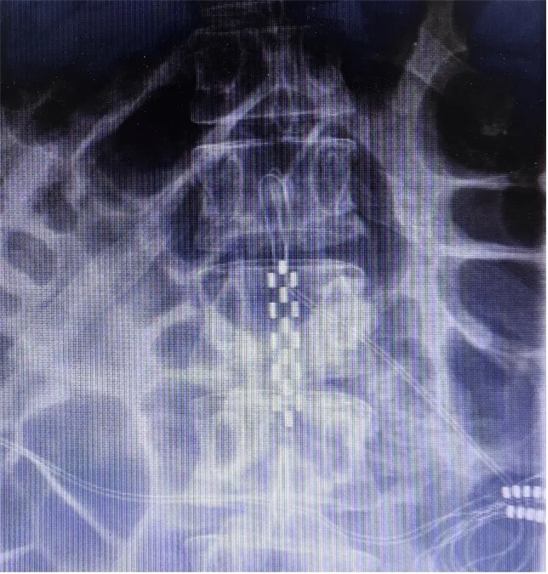

患者长期以来历经康复理疗及药物对症治疗,未见明显疗效,病情仍持续进展,此次专程为寻求脊髓电刺激神经调控治疗就诊。入院后神经调控专业组团队结合文献报道的相关治疗经验,并经过充分的讨论,同意实施脊髓电刺激治疗,以改善病人共济失调步态及平衡障碍。2024年11月20日,夏小雨主任团队为患者实施了胸腰段脊髓电刺激电极植入手术(SCS1期),在术中影像和术中电生理的保障下,1根5-6-5触点电极被准确植入到T12-L1硬膜外。

解放军总医院神经外科医学部派驻第七医学中心神经外科夏小雨副主任医师指出,遗传性脊髓小脑共济失调是一组由基因变异引起的以脊髓和小脑损害为主要临床表现的常染色体显性遗传的神经退行性疾病。2018年5月被纳入中国第一批罕见病目录。目前尚无能有效阻止或减缓SCA进展的治疗方法。目前我们团队将脊髓电刺激(SCS)手术视作一种有效的对症治疗的外科调控手段,它对于疼痛、痉挛、缺血和步态障碍的改善尤其突出、引人注目。国内SCA患者接受SCS治疗后的长期随访有效率令人鼓舞,我们团队也进行了积极的开展。目前,针对步态障碍的控制,SCS电极靶点的位置尚无统一的方案。相较于此前报道较多的T9-11硬膜外,本病例中我们电极埋置的位置相对更低,更接近于腰膨大的末端位置,同样取得了很好的疗效,这个位置主要还是根据术中电生理的结果来确定的。除了脊髓小脑共济失调,我们团队也开展了针对帕金森冻结步态、脑卒中后步态障碍等其他情况的脊髓电刺激治疗,均取得了满意的效果,积累了丰富的经验。